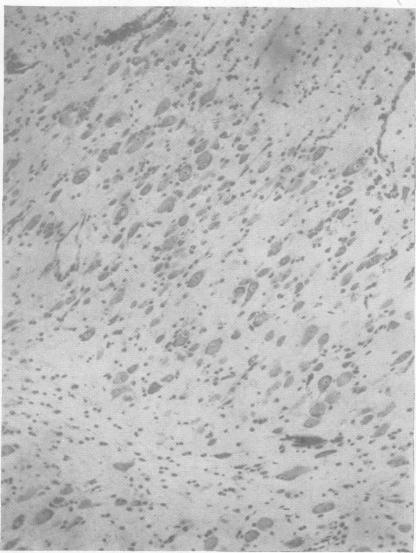

A benign tumour of the cerebellum; report on two cases of diffuse hypertrophy of the cerebellar cortex with a review of nine previously reported cases.

J Neurol Neurosurg Psychiatry. 1955 Aug;18(3):199-213. doi: 10.1136/jnnp.18.3.199.